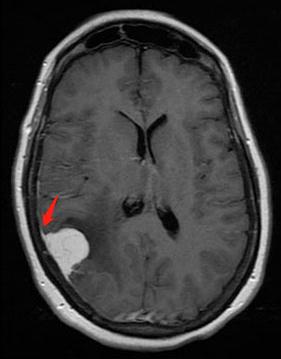

由于这种肿瘤起源于蛛网膜,所以在磁共振检查上面,我们能够看到肿瘤有条“小尾巴”,这是脑膜瘤连在蛛网膜上的“根”

位于额叶的巨大脑膜瘤